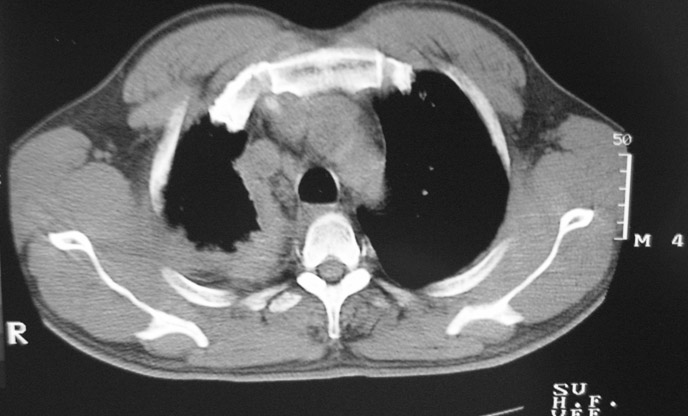

以下是引用守望可可西里在2006-9-11 15:29:00的发言:[br][br] ct平扫表现:右侧胸膜腔缩小,积液,胸膜增厚且不均匀、不规则,以纵隔胸膜增厚为主,边缘呈锯齿状,并见附壁内突之结节状肿块影。右肺含气量减少,纹理聚集,右肺门中下部见数个肿大的淋巴结。纵隔无移位,内未见明显肿大淋巴结,双侧主支气管以及各叶、段支气管比较通畅。。[br] 考虑:右侧胸膜恶性间皮瘤,伴肺门淋巴结转移。